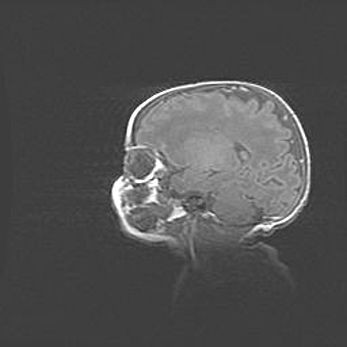

Неполная лизэнцефалия (пахигирия). Открытая гидроцефалия.

Возраст: 17 дней

Вес: 3110 г

Пол: мужской

Окружность головы: 33,5 см

Срок гестации: 35-36 недель

Лизэнцефалия—недоразвитие корковой пластинки и мозговых извилин в результате нарушения миграции нейронов коры. Поверхность мозговых полушарий гладкая. Микроскопически выявляется отсутствие нормальных слоев коры и скопление групп нейронов в подкорковом белом веществе.

Пахигирия—уменьшение числа вторичных извилин. В пораженном полушарии нервные клетки образуют толстый недифференцированный слой с неправильно расположенными нервными волокнами и группами гетеротопных клеток. Нервные клетки незрелые. Белое вещество истончено. При этом нередко аномально развит корково-спинномозговой путь.